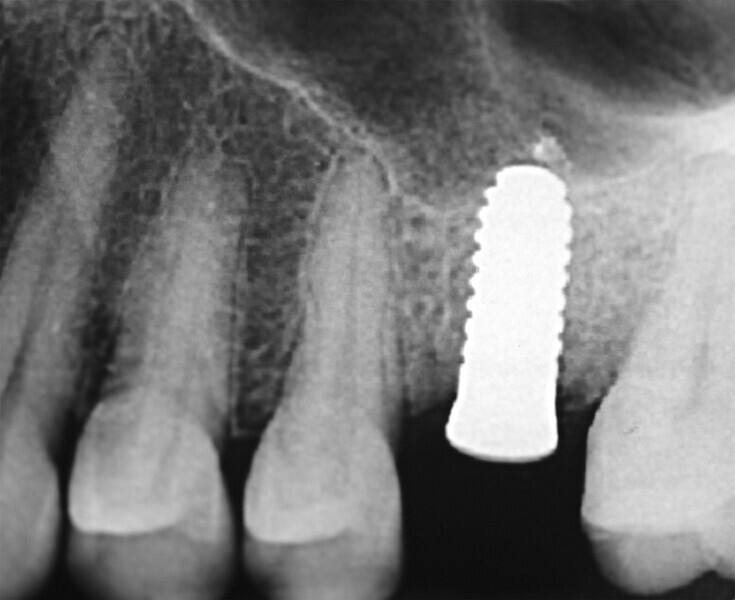

Fig. 44 : Radiographie de contrôle et excellente intégration de l’implant en céramique dans l’environnement parodontal.

Fig. 45 : Radiographie de contrôle et excellente intégration de l’implant en céramique dans l’environnement parodontal.

Un patient présentant un défaut infraosseux s’est présenté au cabinet dentaire avec le souhait explicite d’un traitement par un implant en zircone, pour remplacer l’une de ses molaires. Un implant deux pièces en zircone a donc été posé et le défaut infra-osseux a été traité dans le même temps, au moyen d’une allogreffe osseuse et du dérivé de matrice amélaire Emdogain (Straumann). La mise en charge n’a pas été réalisée à ce stade (Figs. 35–45).